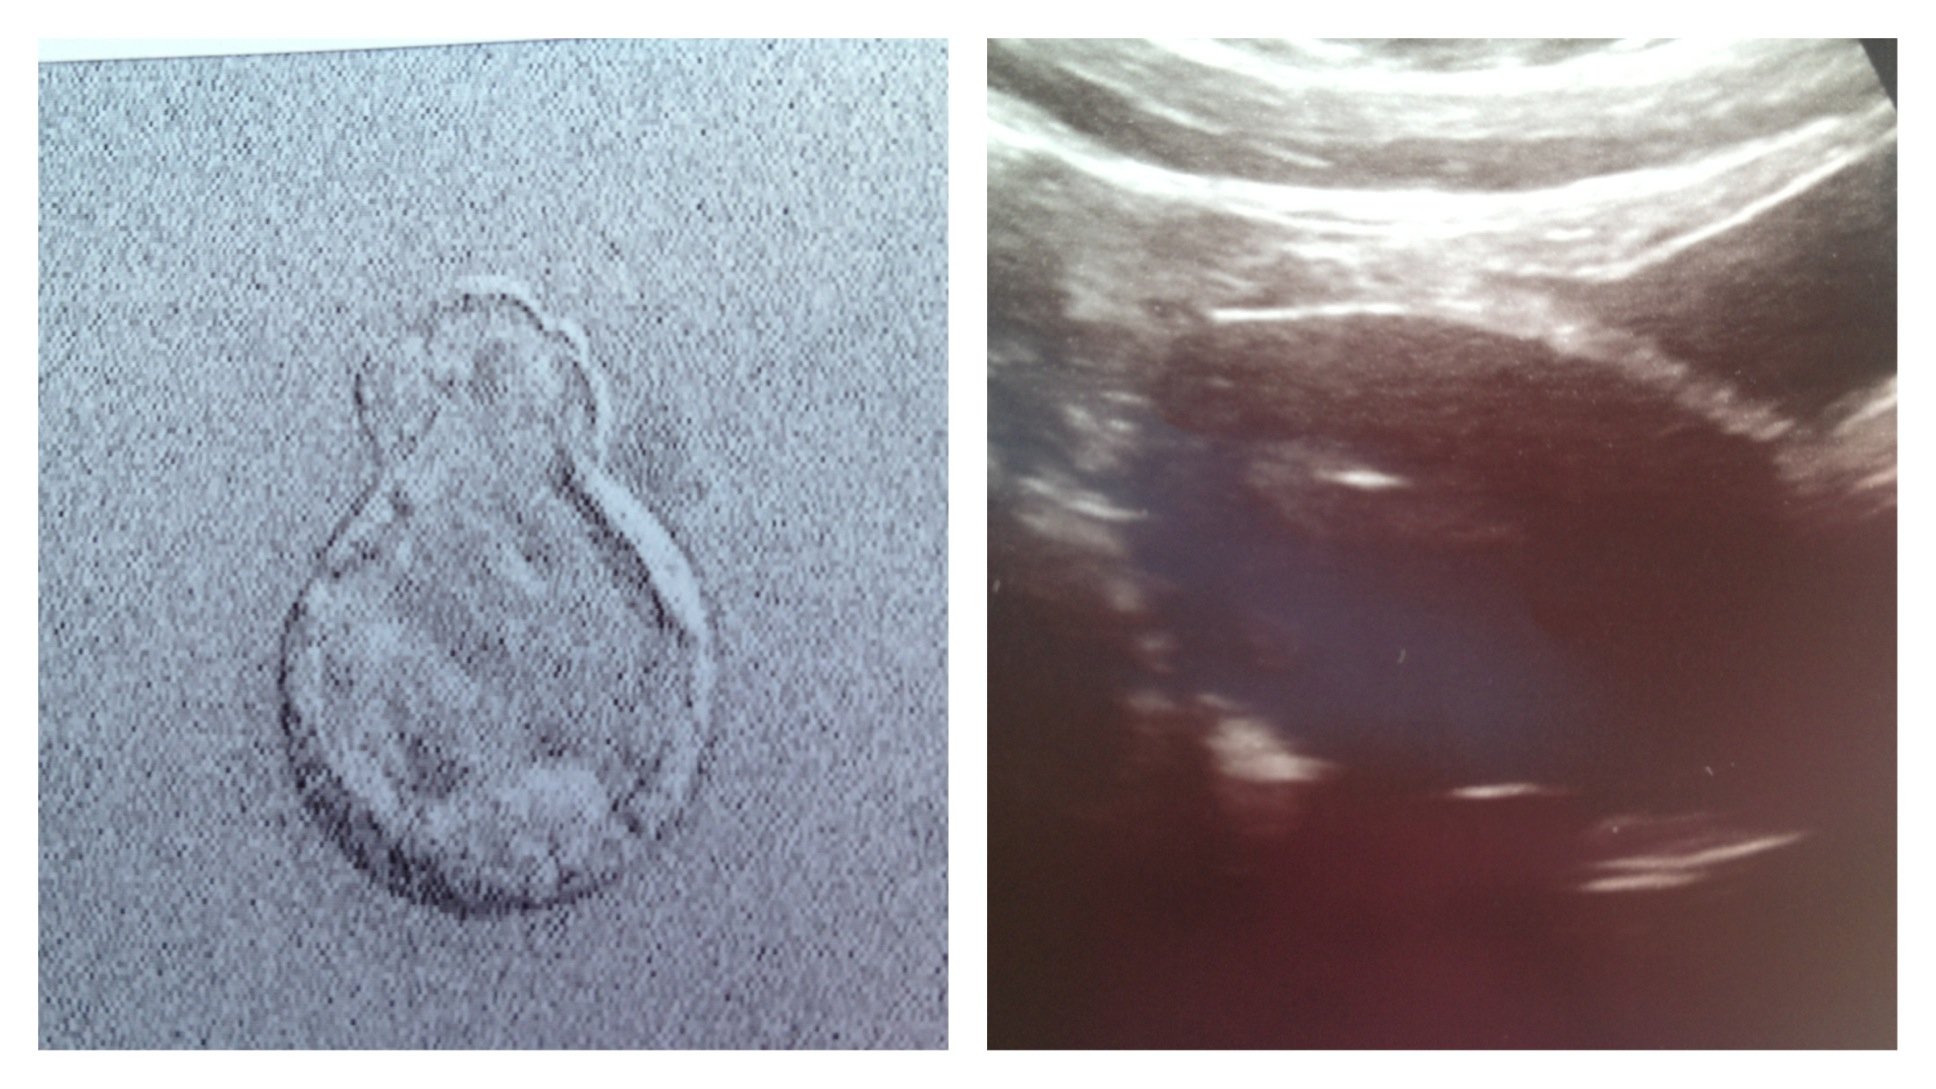

Estrogen than we tried last time. Today is 5dp5dt (10DPO) of one, beautiful, already hatching blast. The picture on the left is the blast hatching after it was thawed. The picture on the right is my ute and you can see the little flash of white on my lining there in the middle. That's the blast being transferred. Isn't science amazing???: